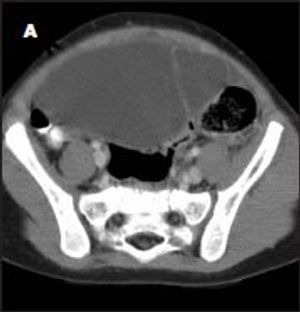

A 2-year-old girl was transferred to the pediatric ICU from a nearby community hospital because of nonremitting, generalized abdominal pain associated with fever and vomiting. Her symptoms had begun 3 days earlier and had progressively worsened despite treatment with antibiotics, pain medication, and fluids.